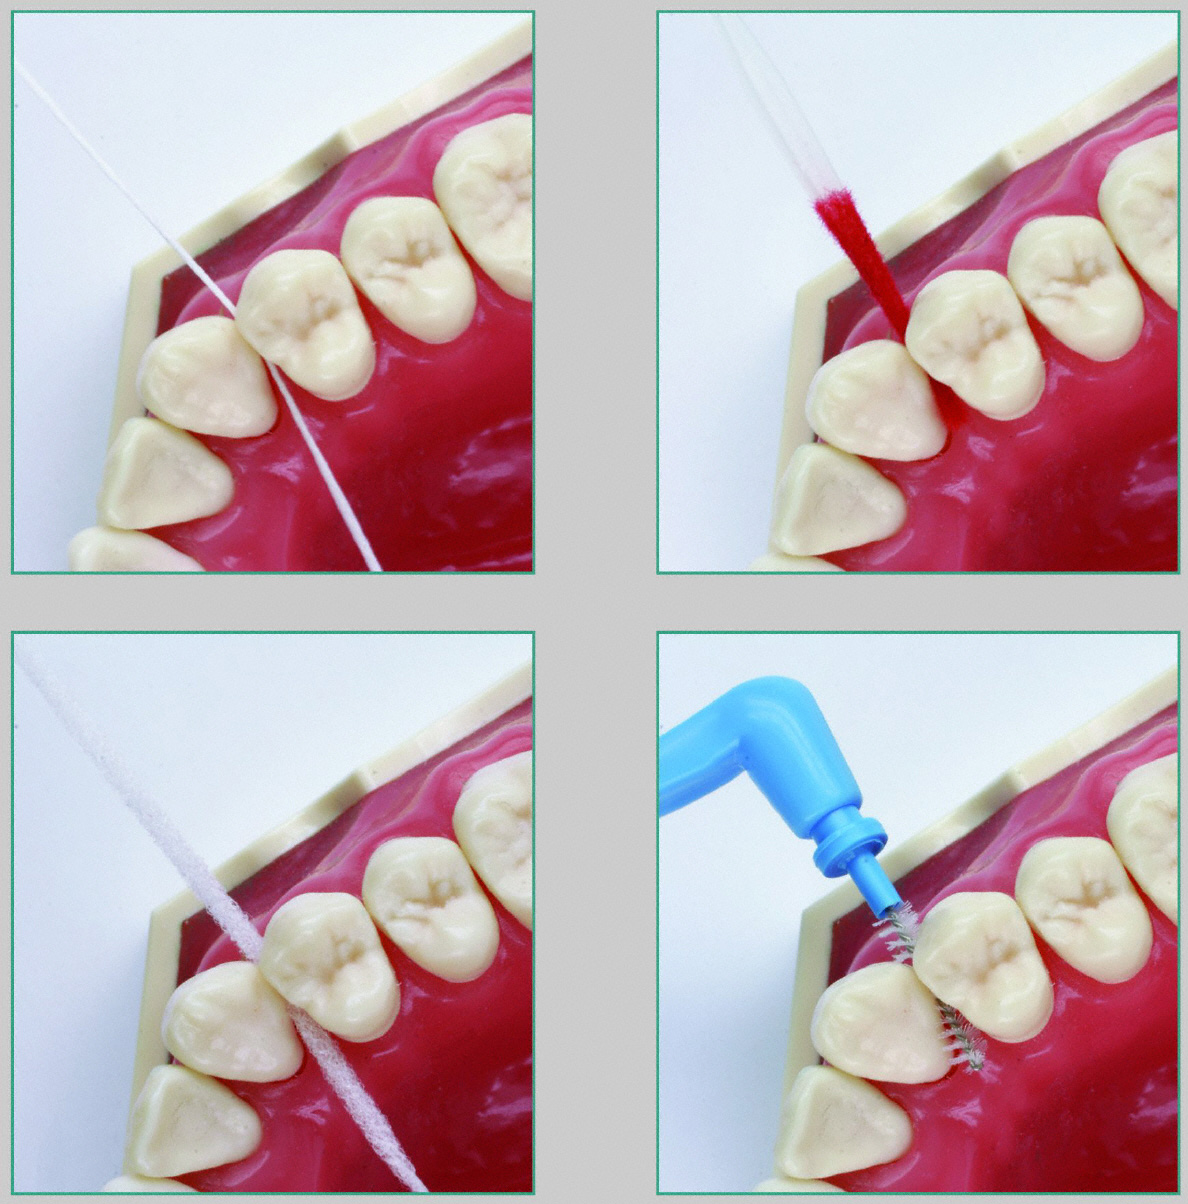

Am wichtigsten ist aber die eigene systematische und regelmäßige häusliche Pflege. Elektrische Zahnbürsten können oszillierend rotierend für gut trainierte Patienten oder schallaktiv für untrainierte Patienten sein. Bei Parodontitis-Patienten ist der Interdentalraum in der Regel erweitert und daher besonders zu beachten und zu behandeln. Für die möglichst langfristige Erhaltung des Behandlungsergebnisses ist die systematische, regelmäßige und intensive Säuberung des Zwischenraumes eine wichtige Voraussetzung. Dazu braucht der Parodontitis-Patient Hilfsmittel wie Zahnseide, Zahnhölzer, Flauschzahnseide und Interdentalbürstchen.